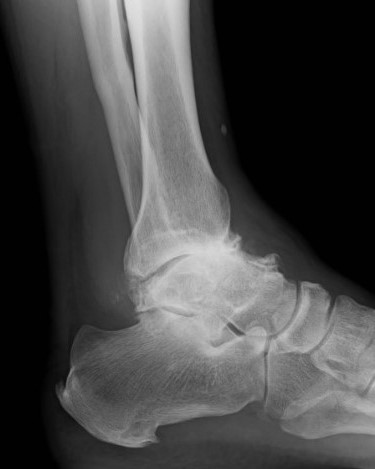

変形性足関節症

変形が軽度であれば装具療法(インソールやサポーター)、投薬、関節注射を行っています。変形が高度で痛みが強い場合は、関節固定や人工足関節置換術 (図1、2)などを行っています。

術前

術後

図1 : 人工足関節置換術